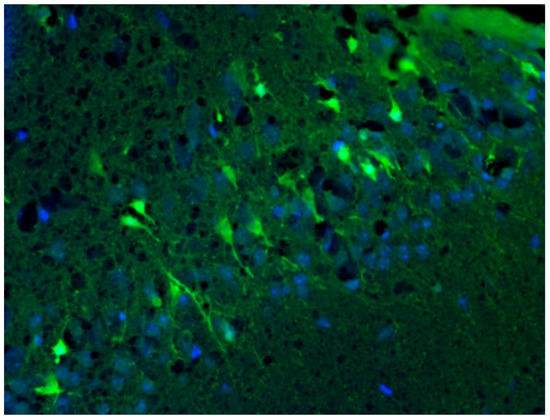

2.7. Detection of Neurodegeneration Localization Using Fluoro-Jade C Dye

3.7. Analysis of Intensity of Neurodegeneration in KA-Induced Experimental Epilepsy Model

3.8. Analysis of Localization of Neurodegeneration in KA-Induced Experimental Epilepsy Model